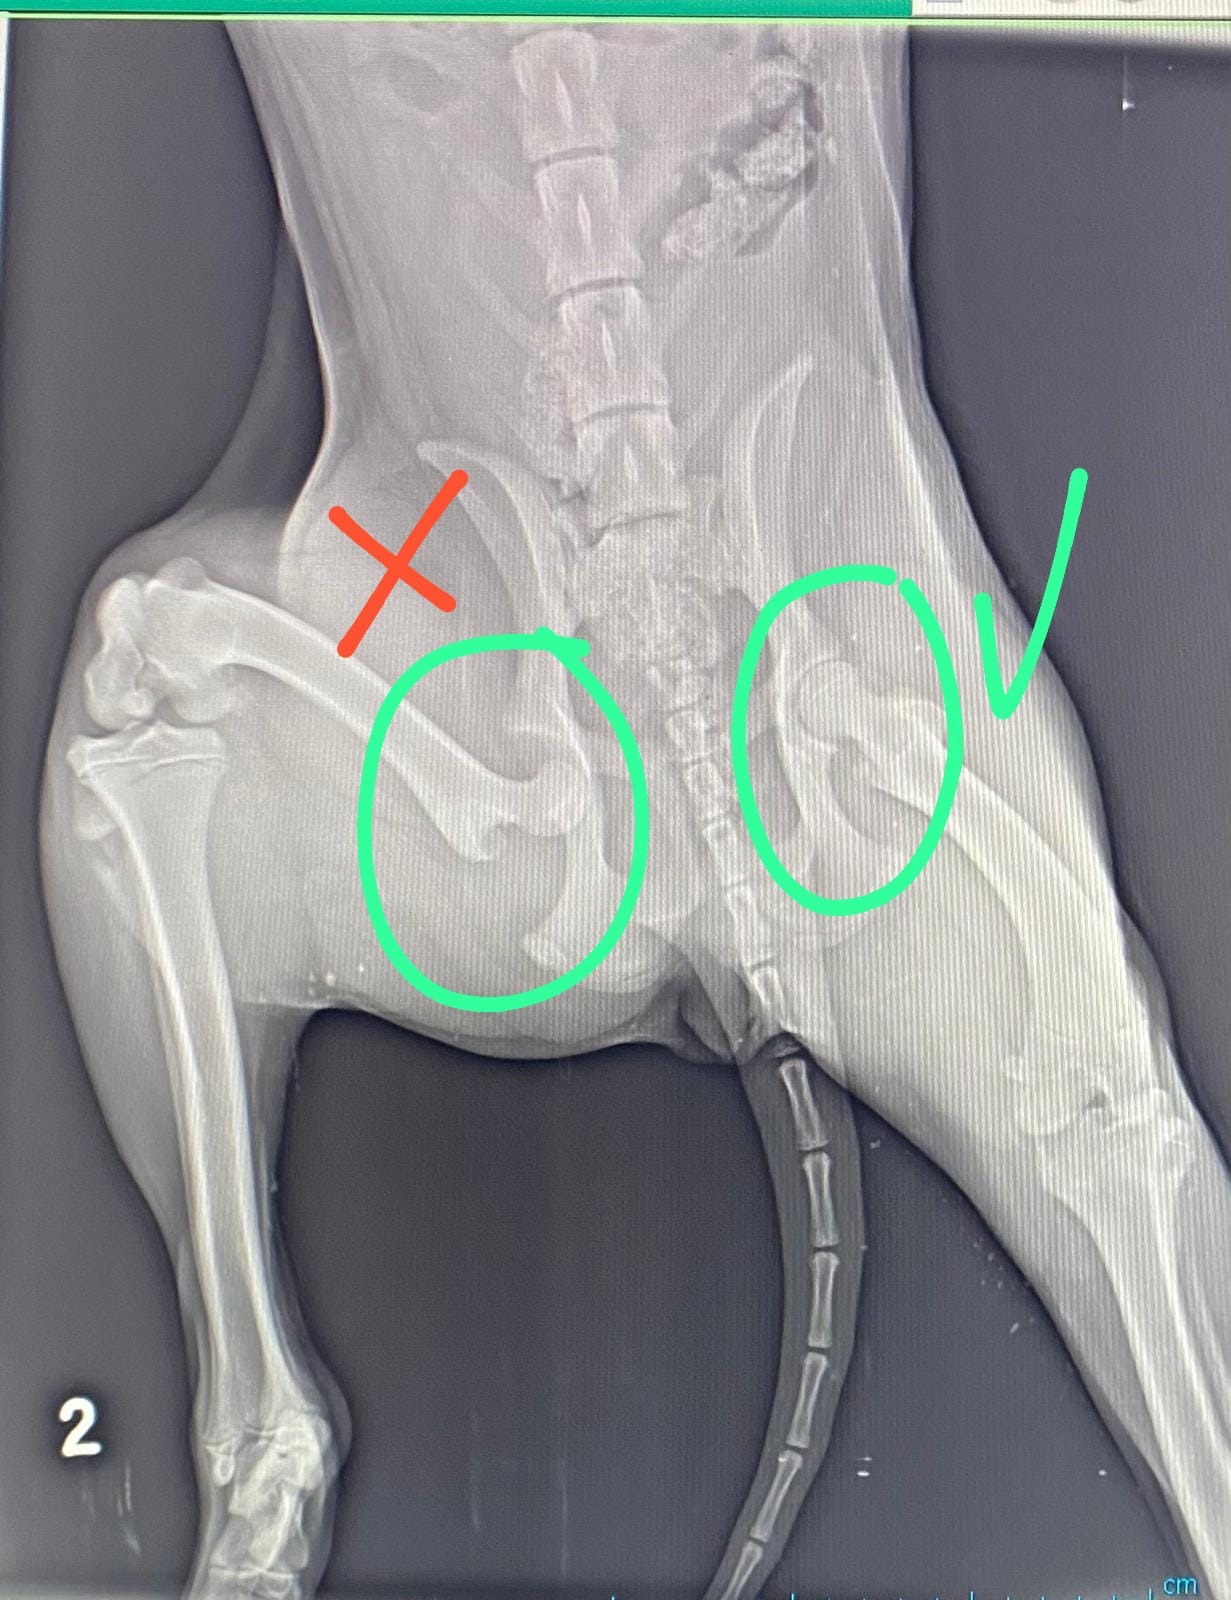

Post-surgery update on Sol

Sol is healing! We’ve added two photos: one shows her surgical site, which is being carefully treated with Canocept wound spray. The other shows her sweet face, which is just as strong and stubborn as ever.

She survived, with a broken hip.